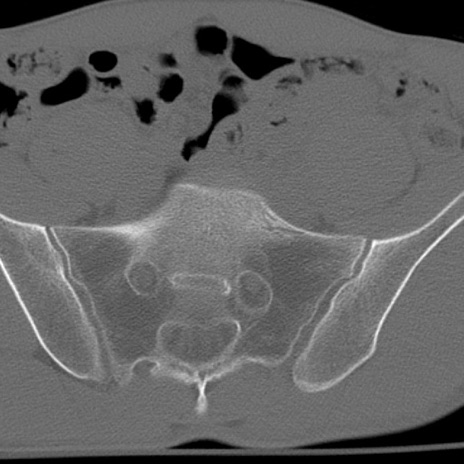

症例3 腰椎CT(横断像)

腰椎CT